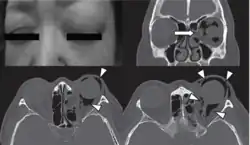

Physical examination

Physical examination of the eyelid can be done by the palpation for the pathognomonic cracking, crepitation,[11] and tense tissue[35] on the upper and lower eyelids. The findings of the examination are supported with the medical history of the patient and confirmed with orbital CT.[6]

Computed tomography (CT)

Computed tomography is effective and sensitive in the diagnosis of orbital emphysema,[3][37] as it can confirm the anatomical location and size of air, bony defects, indentation of the eyeball, and the condition of the optic nerve, as well as the presence of any extraocular muscle entrapment and herniation of preorbital fat into the sinus cavities.[3][15][38] The location of the orbital emphysema is present near the site of the fracture.[1][3] The scans are usually taken along the transverse plane. Transverse images allow the evaluation of fractures in medial and lateral orbital walls. By reformatting these transverse images or taking coronal images, the examination of orbital floor and roof is permitted. Helical scanning is preferred as it has a lower imaging time and radiation dose comparing to conventional scanning, especially when reforming transverse helical scans into coronal images.[3] The staging of orbital emphysema can then be determined with visual acuity examination and ophthalmoscopy.[6] A disadvantage of using a CT scan is that when detecting air after orbital trauma, the presence of a wooden foreign object can give a false positive result of orbital emphysema. The wooden object can mimic the presence of orbital emphysema. Therefore, patients’ medical history is crucial in making the correct diagnosis.[3]